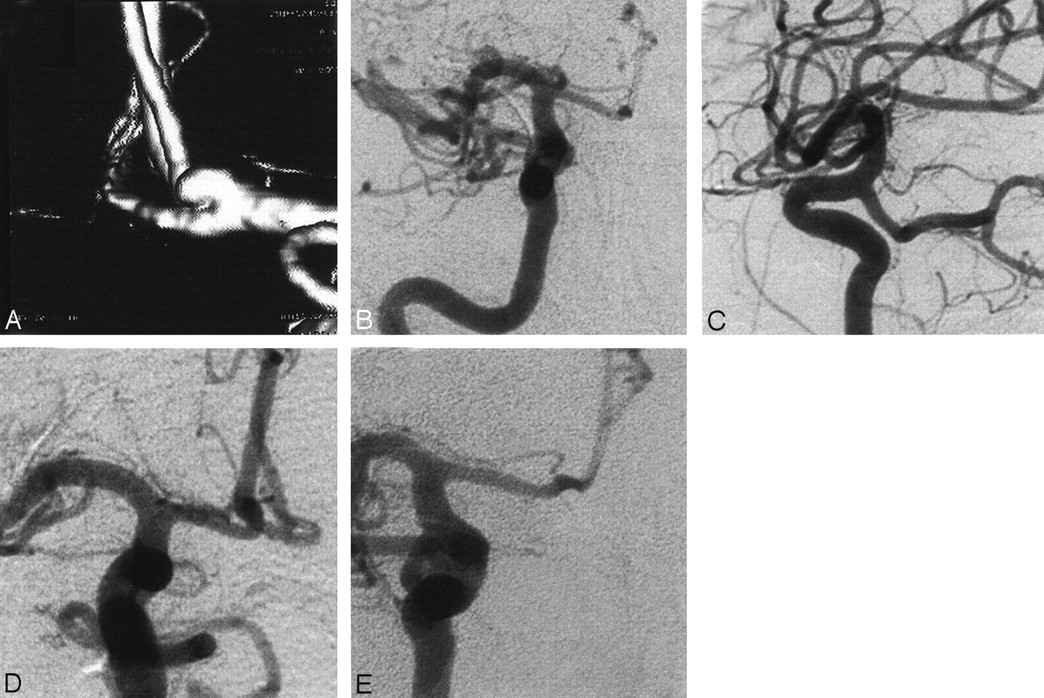

Angiograms in a patient with SAH Hunt and Hess grade II.

A–C, SSD-reconstructions.

D–F, DSA series in an aneurysm in the bifurcation of the middle cerebral artery. The extent, neck, and spatial relationship of the aneurysm to the neighboring and parent vessels was reliably demonstrated at RA.